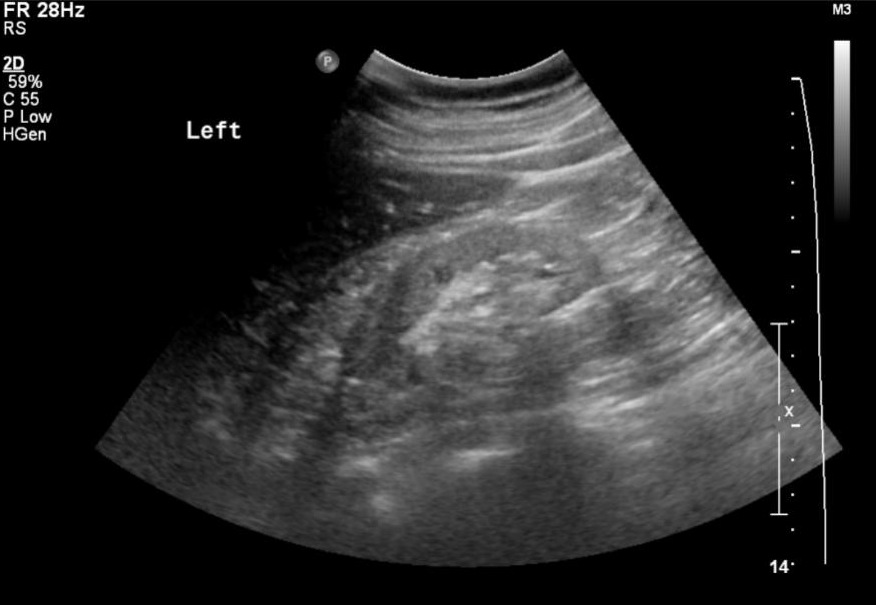

胸部 CT 显示 “两肺水肿”,双肾 B 超提示 “双肾回声增强、边界模糊”,进一步印证慢性肾损伤与心功能受累。

▲患者影像学检查